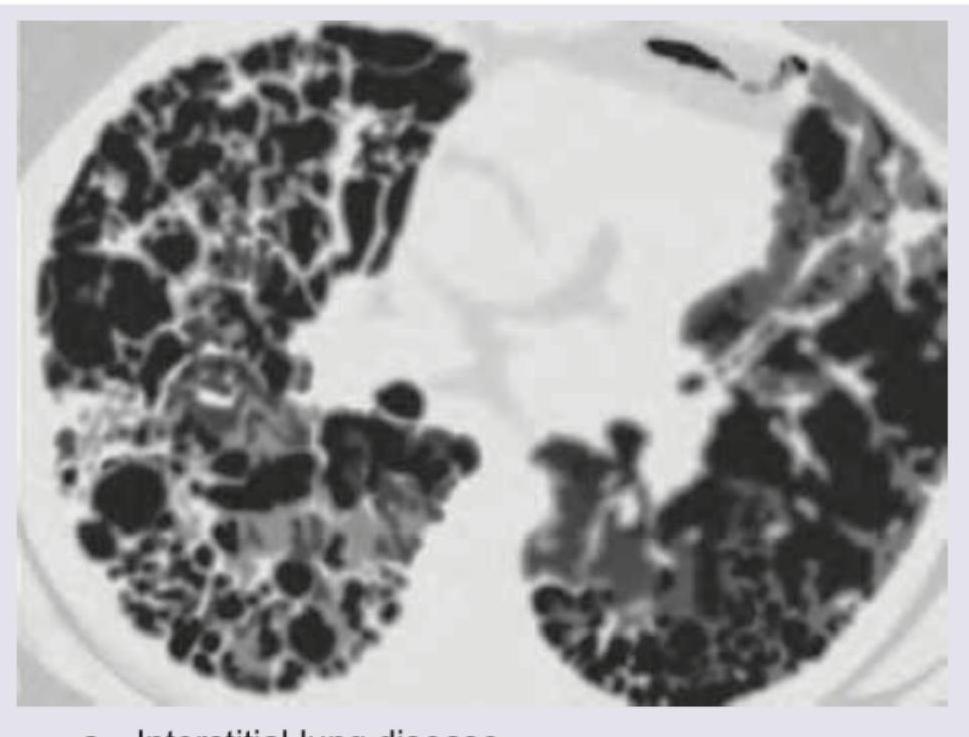

Explanation: ***Pulmonary alveolar proteinosis*** - CT images of pulmonary alveolar proteinosis often show diffuse, bilateral ground-glass opacities with superimposed **interlobular and intralobular septal thickening**, creating a characteristic **crazy-paving pattern**. - This pattern, as seen in the image, is caused by the accumulation of lipoproteinaceous material within the alveoli and is a hallmark of the disease. *Interstitial lung disease* - While some forms of interstitial lung disease can cause ground-glass opacities and septal thickening, the **"crazy-paving" pattern** seen so clearly and diffusely here is not typically their most characteristic finding. - ILD often presents with **reticular opacities**, honeycombing, or traction bronchiectasis, which are less prominent or absent in this specific image. *Bronchiectasis* - Bronchiectasis is characterized by **irreversible dilation of the bronchi**, usually accompanied by wall thickening. - This condition would appear on CT as **dilated, thickened airways** (often described as "tram-track" opacities or "signet-ring" signs) and mucus plugging, which are not the predominant findings in the provided image. *Aspergillosis* - Pulmonary aspergillosis encompasses several forms, such as aspergilloma (fungus ball in a cavity), invasive aspergillosis (nodules, halo sign, or cavitation), or allergic bronchopulmonary aspergillosis (mucoid impaction, bronchiectasis). - The diffuse ground-glass opacities with septal thickening seen in the image do not typically represent the primary radiological features of aspergillosis.